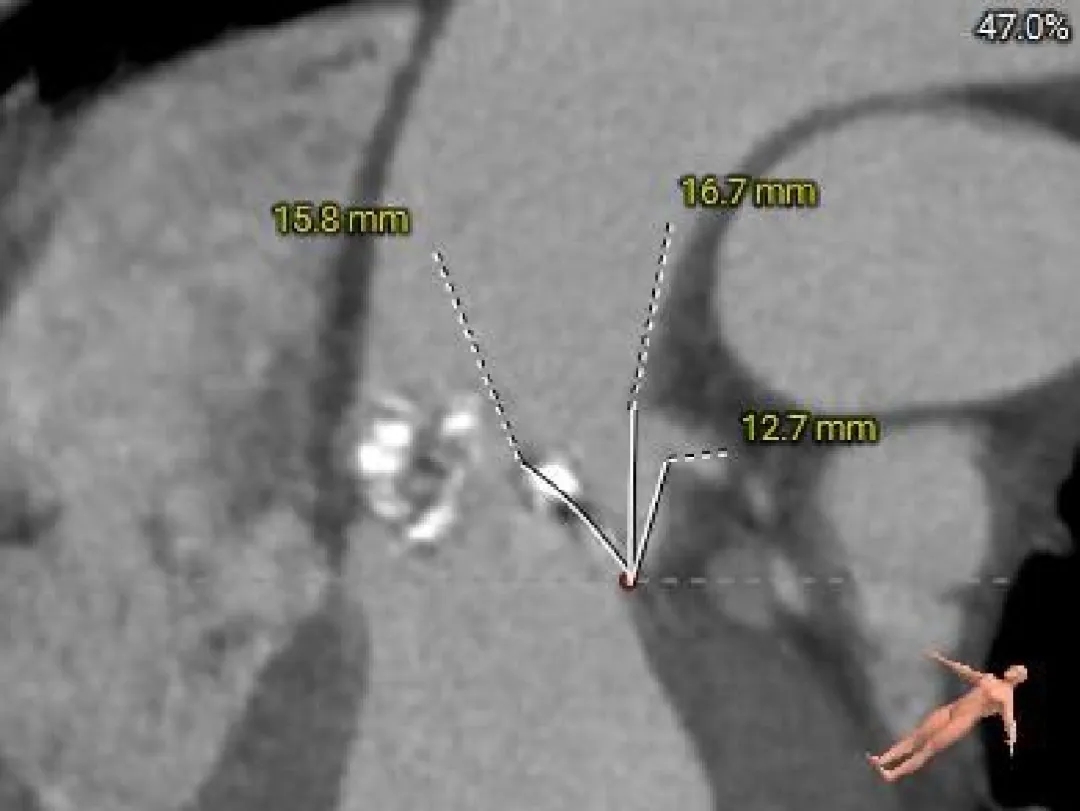

Left Coronary

12.1mm

LCA & Leaflet

12.7mm<15.8mm

-

双侧冠脉开口高度可

左、右冠瓣叶长度>冠脉开口下缘到根部距离

结合SOV、STJ测量,窦部空间较小,预估冠脉阻挡风险较高